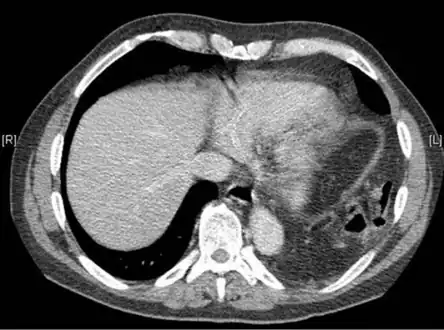

Bilateral blunt diaphragmatic rupture a) confirmation of intrathoracic herniation indicates left hemidiaphragmatic rupture b) post operative image shows elevation of right hemidiaphragm adding suspicion of right diaphragmatic rupture -

Axial lower chest CT scan showing bowel herniation due to left diaphragmatic rupture